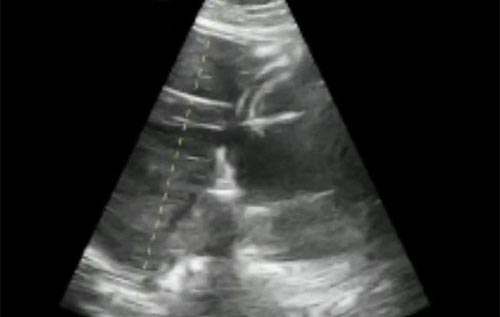

Semana 13

Como diferenciar veia de artéria pela imagem acima?